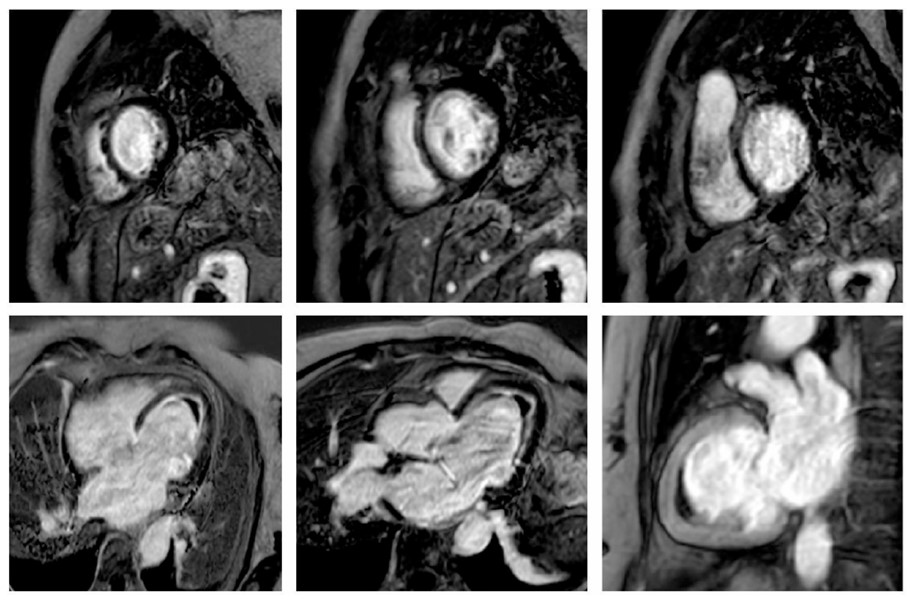

The study was completed with Cardiac Magnetic Resonance (CMR) imaging, which additionally revealed myocardial edema and extensive endocardial fibrosis in the LV, both diffuse and predominantly located in the mid-apical and inferolateral walls (Fig. 3).

Cardiac magnetic resonance T1-weighted sequences following gadolinium-based contrast administration demonstrate diffuse ring-like endomyocardial enhancement in the left ventricle, predominantly involving the mid and apical segments, as well as the basal inferolateral wall. These findings suggest extensive endocardial fibrosis, apical obliteration due to intraventricular thrombus, and incipient basal aneurysm formation. Extensive myocardial edema is also evident on the final T2-weighted sequence. Taken together, these findings are highly indicative of active eosinophilic myocarditis.